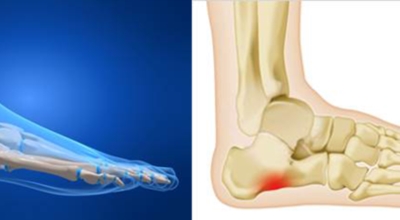

족저 근막이란 발가락 시작지점부터 발뒤꿈치뼈까지 발바닥 전체를 감싸고 있는 두꺼운 막을 말합니다. 족저 근막은 발바닥 아치를 지속시켜 발바닥이 지면을 내딛음으로써 발생하는 충격을 흡수하는 중요한 역할을 수행하고 있답니다. 이 족저 근막에 일차적으로 서서히 조직 손상이 일어나고 계속적인 활동으로 말미암아 염증이 커지면서 발 뒤꿈치 부근 통증을 일으키게 되는데 염증은 무리하고 반복적인 동작, 많은 사용으로 마찰에 의해 발생합니다.

족저 근막염은 염증에 의한 손상 및 통증을 유발하는 질환인데요 족저 근막염 증상은 일반적인 발뒤꿈치 통증 하글런드 병변의 기형으로 알려져 있으고 아킬레스 건과 관련이 깊다고 합니다. 특히 근육이 덜 풀린 아침 시간 대는 보행 시 날카롭고 바늘로 찌르는 듯한 심한 통증을 느끼게 된다고 합니다. 하지만 아침 시간 대를 지나 오후에 접어들면서 어느 정도 통증은 서서히 감소하기 시작한다고 하는데요 초기 증상이 나타난다면 꼭 전문의를 찾아 조기치료하는 것이 바람직합니다.